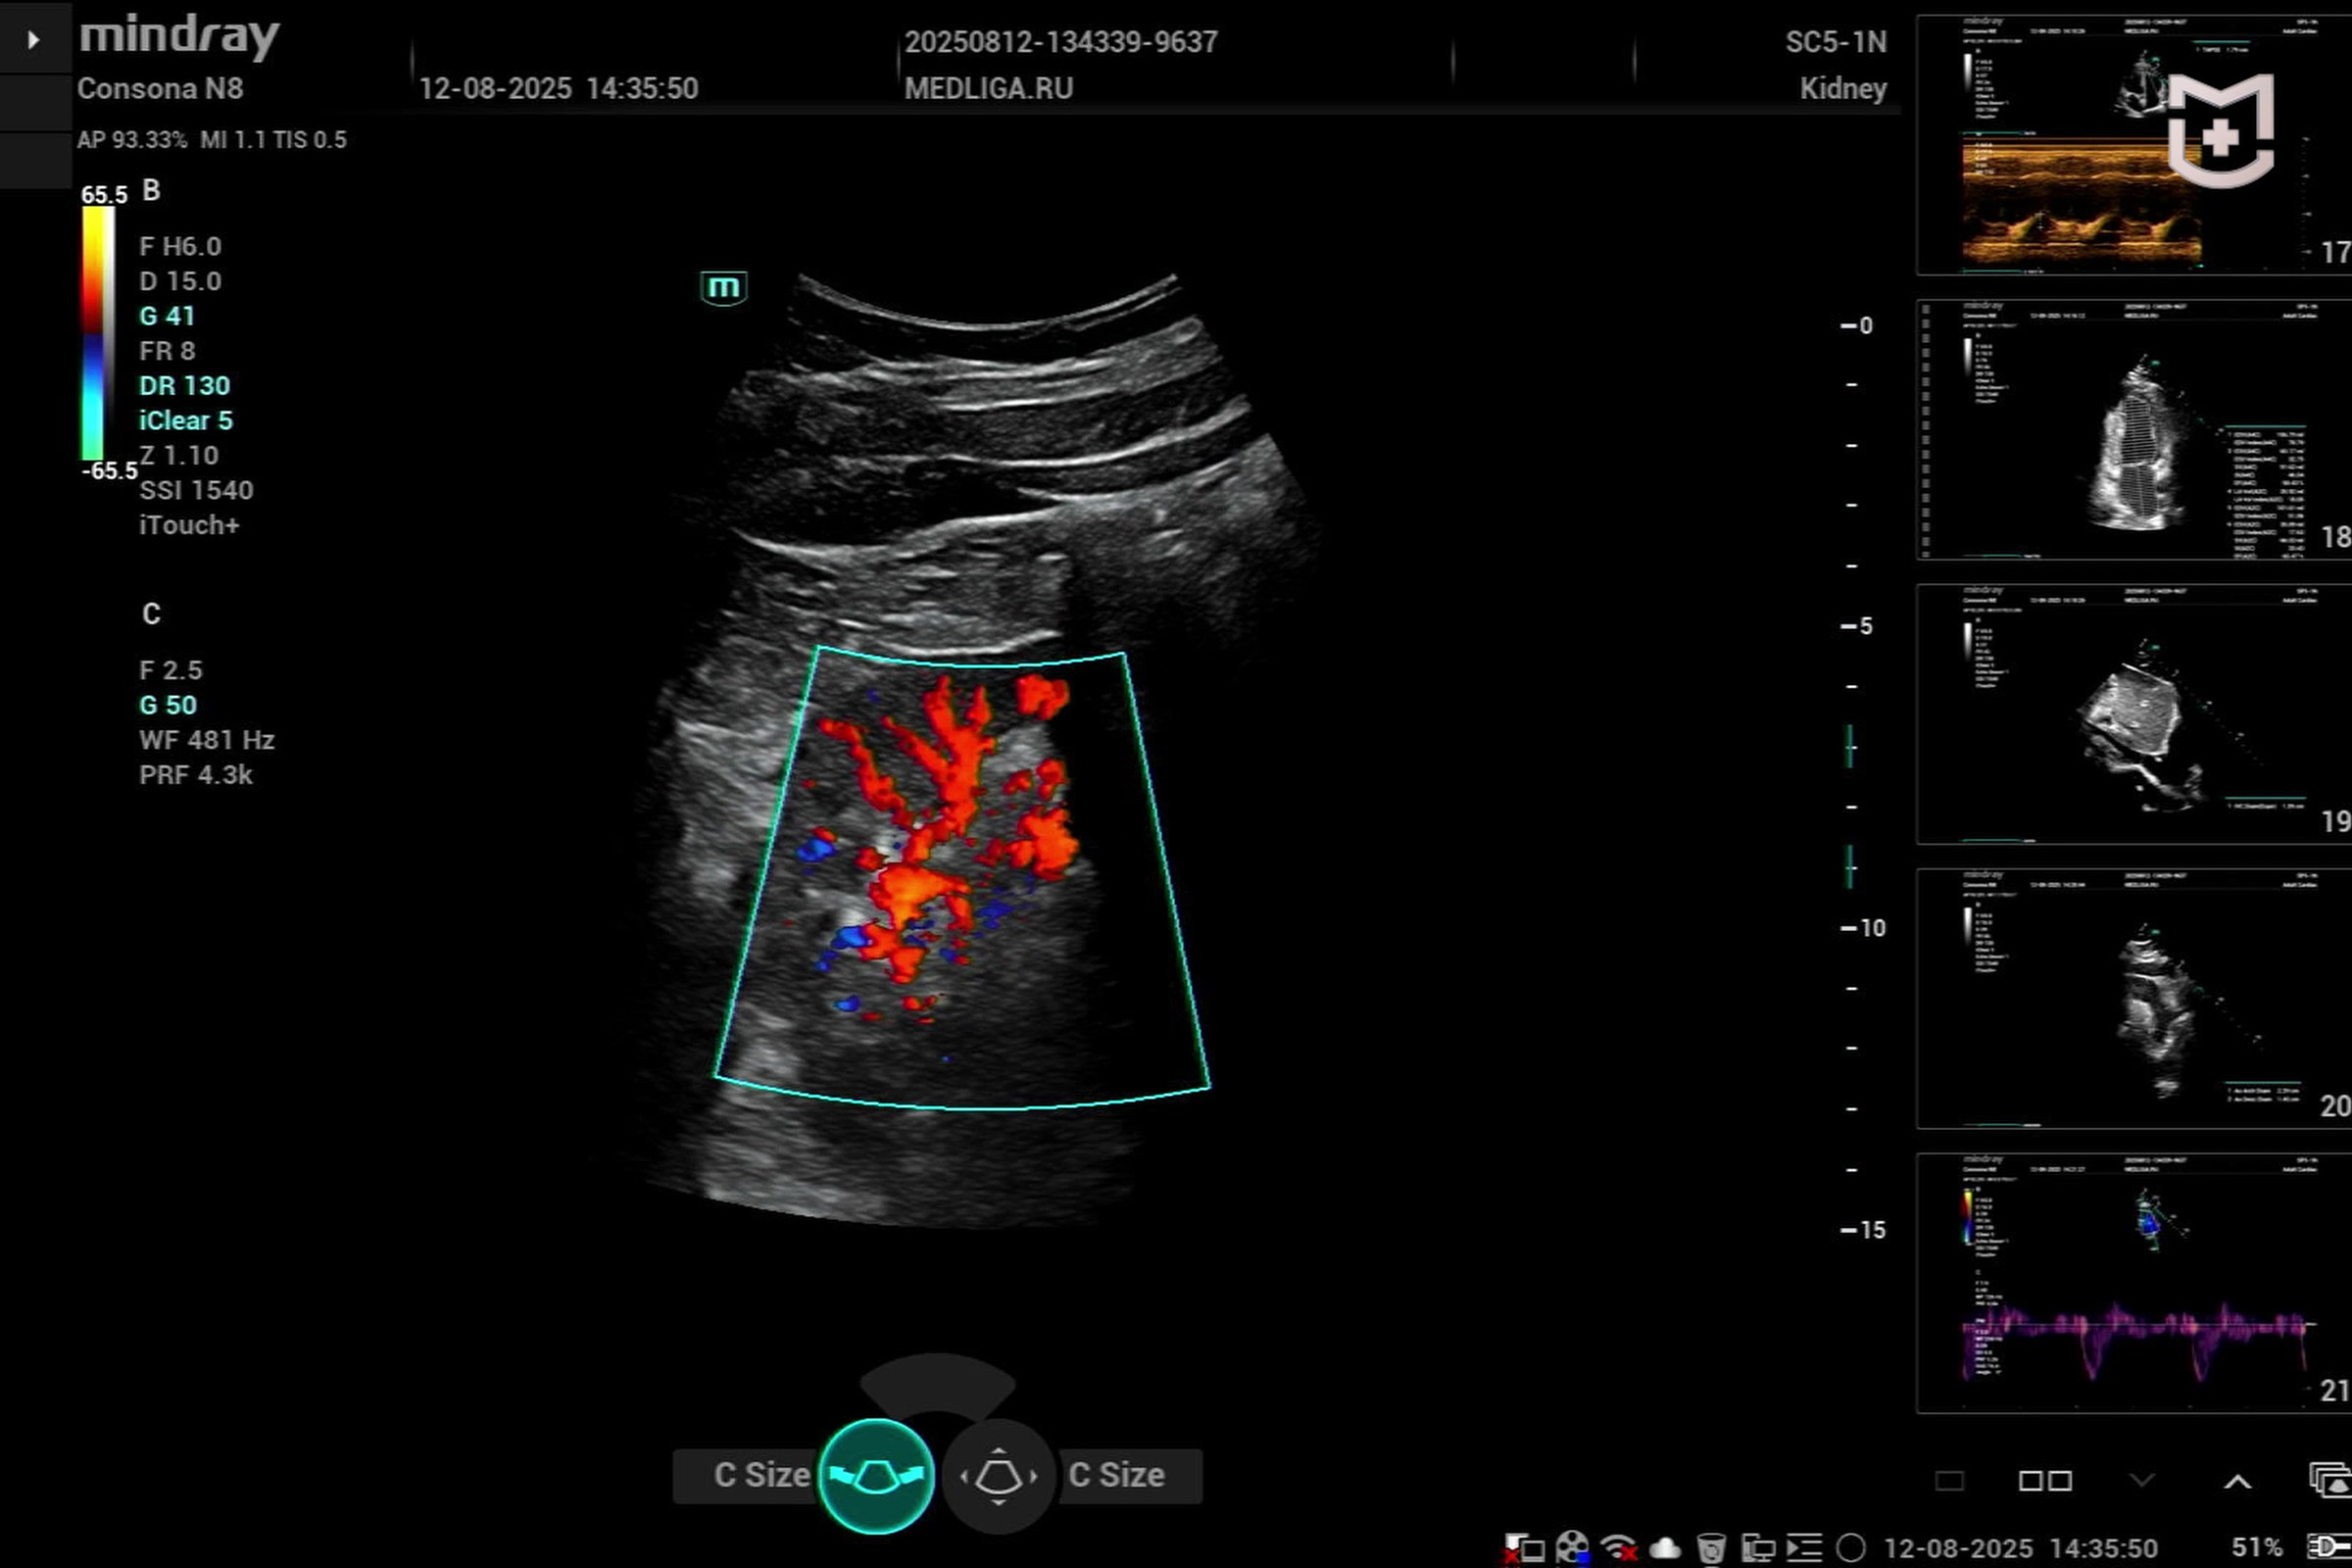

Медицинское оборудование для ультразвуковой диагностики